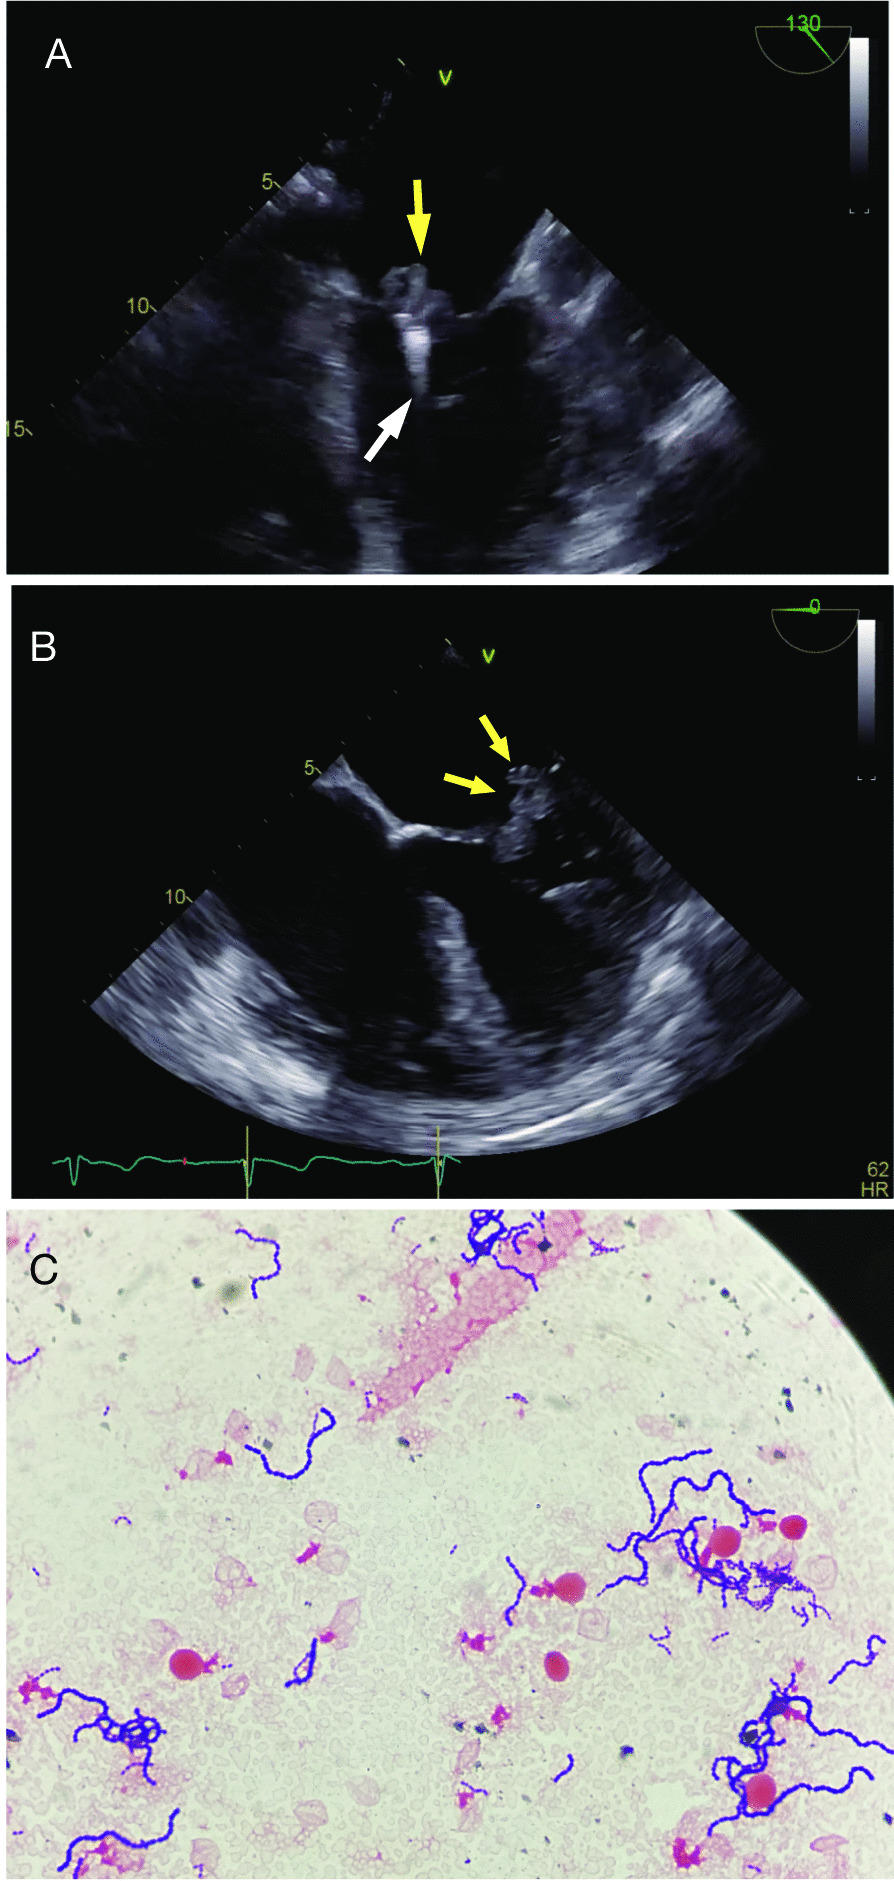

Upon arrival, the patient was alert and fully oriented, without signs of respiratory distress, and oxygen saturation 96 % on room air. However, he was febrile (38.6 °C) and hypotensive (blood pressure 81/45 mmHg). On physical examination, there was a loud holosystolic murmur at the apex radiating to the axilla, bilateral pitting edema in the lower extremities, and elevated jugular venous pulsation. Laboratory studies revealed elevated white blood cell count (20.5 K/µL with a left shift), creatinine (2.1 mg/dL), and lactic acid (2.4 mmol/L). An X-ray and computed tomography of the chest were unrevealing. A bedside transthoracic echocardiogram showed severe MR with a possible echodensity on the mitral valve. This finding prompted a transesophageal echocardiogram, which demonstrated a 2.0 × 0.8 cm pedunculated, mobile vegetation on the P2 segment of the posterior leaflet of the mitral valve on the MitraClip as evident from Fig. 1A, B and the transesophageal echocardiogram movie clips (Additional file 1: Video S1, Additional file 2: Video S2, Additional file 3: Video S3).

Fig. 1.

A Mid-esophageal long axis view on transesophageal echocardiogram (TEE) showing the MitraClip device (white arrow) and a large pedunculated mass consistent with vegetation (yellow arrow) on the atrial surface of the mitral valve. B Mid-esophageal 4-chamber TEE view showing a large vegetation (yellow arrows) on the atrial surface of the posterior mitral valve leaflet. C Gram positive cocci in chains seen on a gram stain of a positive blood culture

Five sets of blood cultures were collected during the first two days of admission and all grew gram positive cocci in pairs and chains which were later identified as Streptococcus oralis (Fig. 1C), by matrix-assisted laser desorption/ionization (MALDI) technique, with minimum inhibitory concentration (MIC) to penicillin 0.06 mg/L (Vitek® 2, bioMerieux, Durham, NC). The patient was initially started on empiric antibiotics with vancomycin and cefepime, which were switched to ceftriaxone 2 gr once a day, when the blood culture results, and antibiotic sensitivities became available. Subsequent blood cultures remained negative. The patient did not develop signs or symptoms of a secondary lesion (e.g., stigmata of endocarditis) and no further systematic work up for metastatic lesions was performed. During the first 48 h of his admission, following fluid resuscitation, the patient developed pulmonary edema with worsening hemodynamic instability requiring vasopressor support. Although toxic shock syndrome was considered, as the patient had hypotension and renal impairment, there were no additional criteria for this syndrome, and thus his deterioration was felt to be secondary to cardiogenic rather that septic shock. Cardiothoracic surgery was consulted for potential removal of the clips and mitral valve replacement. However, because of multiple comorbidities, the patient was considered of prohibitive surgical risk. Therefore, the decision was made to continue medical management with intravenous ceftriaxone for 6 more weeks and possibly lifelong oral antibiotic suppression therapy. Despite a marginal improvement in clinical status with appropriate antibiotic therapy, the patient remained in a fragile hemodynamic and fluid management balance, struggling to control hypoperfusion, renal impairment, and elevated cardiac filling pressures. Eventually, palliative care discussions with the patient and the family led to the decision of comfort-directed care. The patient died a week later.